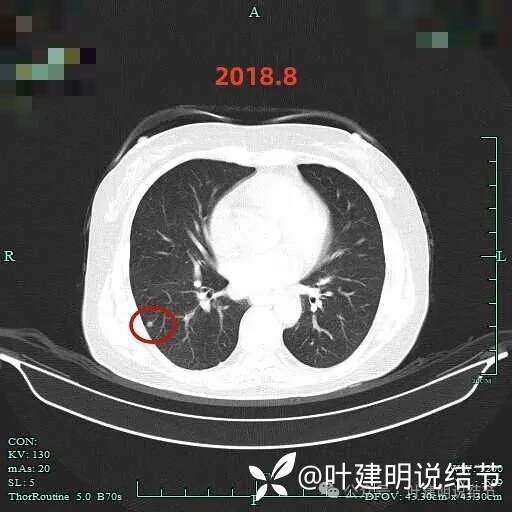

2018年8月时右下病灶似乎不是太纯,轮廓清楚,大小仍小。